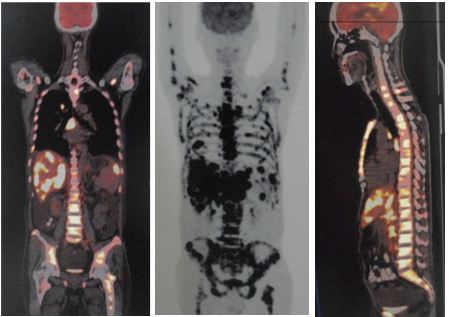

MRI on 2 October indicated:

- T4 pathological facture causing compression on the thecal sac and spinal cord.

- T2 – T7 and S1 – S2 metastatic vertebral lesions.

- mild L4/5 posterior disc bulge.